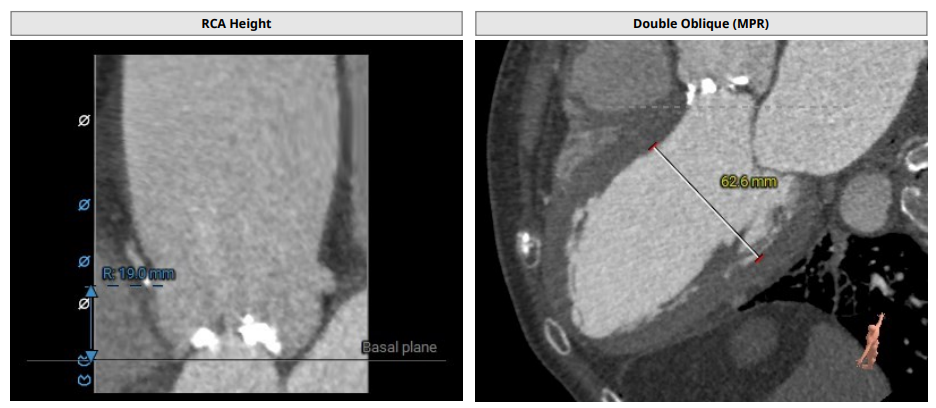

CT分析

TYPE0型二叶瓣,瓣叶增厚,重度钙化,左冠开口高度约18.5mm,右冠开口高度约19mm,法式窦结构大,STJ高度约25.4mm、直径约42.2mm,升主动脉增宽,最宽处约56 mm,心脏角度约60°,左室大。

主动脉根部解剖及入路分析